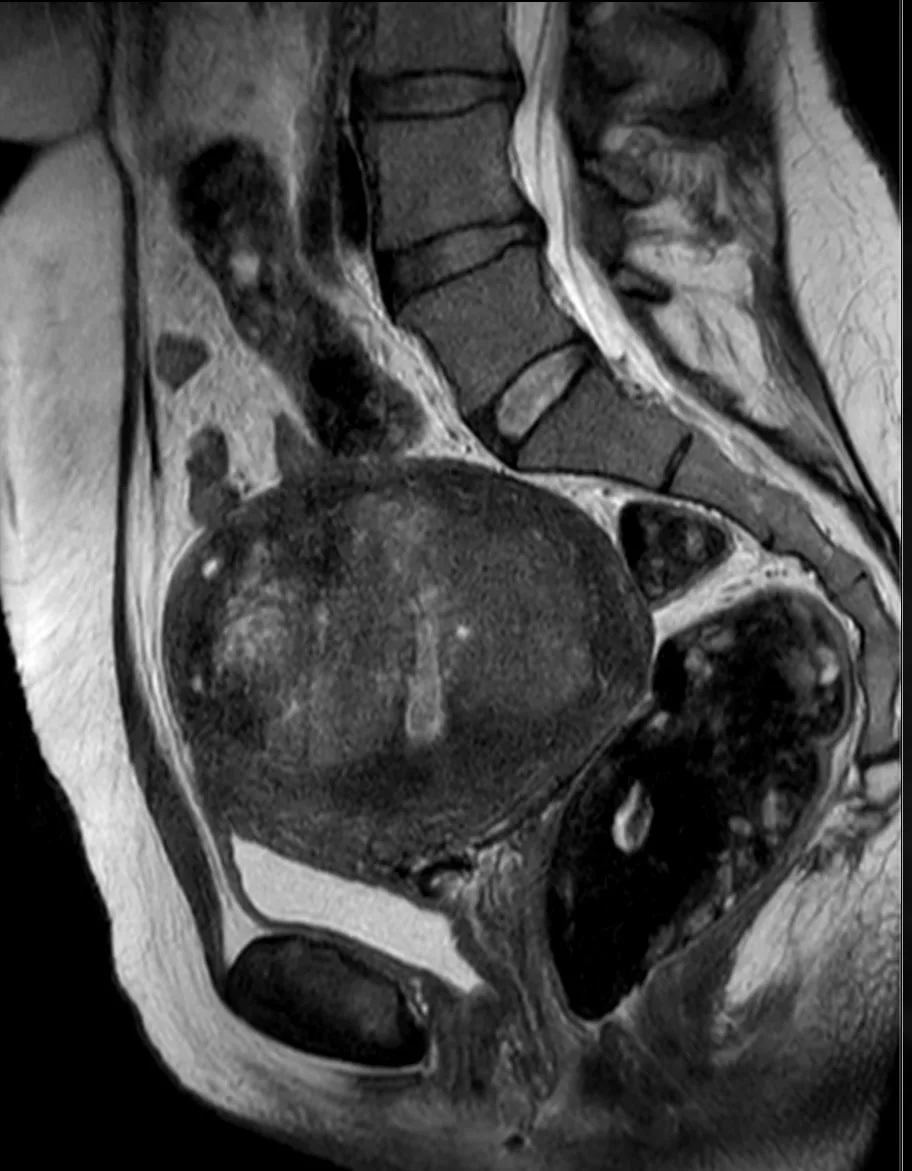

Классные тератомы. 30 лет.

В ОРАЦ есть интересный момент: когда речь о тератоме, то надо оценить, есть ли значительное количество ткани, накапливающей контраст. Субъективная вещь. Один сочтёт, что значительное, другой сочтёт, что не значительное. Но в первом случае это будет четвёртая категория и опухоли надо удалять, а во втором случае это будет вторая категория, и можно просто спокойно понаблюдать. Только что переубедил коллегу написать двойку вместо четвёрки по этим картинкам.

Кривую показываю на всякий случай, она на присвоение категории в данном случае не влияет, но дополнительно успокаивает, что ли. А зубчатость её объясняется тем, что исходные изображения и изображения после субтракции представляют собой одну серию, а вручную их разделять мне было лень. На информативность кривой это никак не влияет.

Видно, что в миометрии контраст накапливается гораздо быстрее и гораздо сильнее. То есть, если бы это на что-то влияло, то эту кривую надо было бы расценить, как кривую низкого риска.